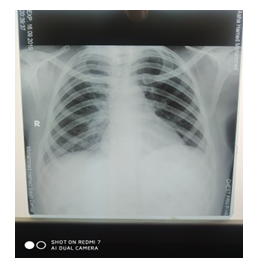

After one month TFT was done again and it was normal, TSH 0.47mIU/L (normal rage 0.38-4.3) T4 was 6.1nmol/L (normal rage 4.9-11) T3 was 0.78nmol/L (normal rage 0.79 – 1.58) and chest X-Ray (Figure 2) was normal. The patient continued to be followed up monthly, and showed a good outcome.

Figure 2 Chest X-ray Normal.